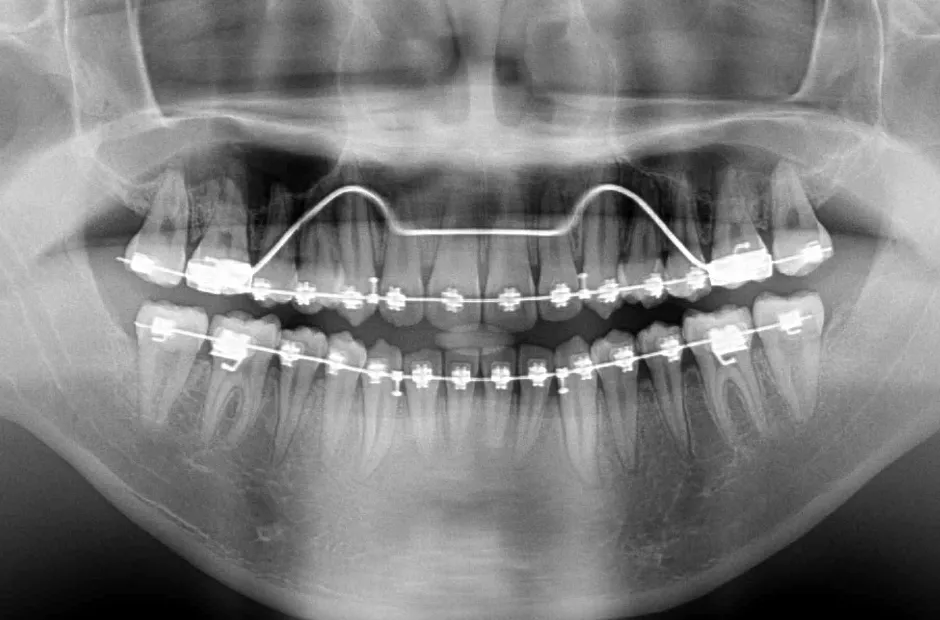

叢生

| 診断名・主訴 | 叢生 |

|---|---|

| 年齢・性別 | 43歳・女性 |

| 治療期間・回数 | 2年7か月 27回 |

| 治療に用いた主な装置 | 舌側矯正 |

| 抜歯部位 | 両顎4,4 |

| 治療費 | 100万円(税抜) |

| リスク・副作用 | 装置による違和感・疼痛・歯肉退縮・歯根吸収・虫歯のリスクなど |

治療中

治療後